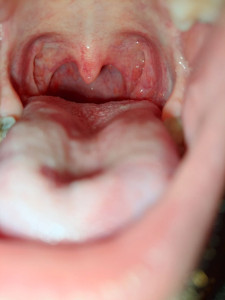

Здравствуйте подскажите пожалуйста.

Болею третий день вирусной инфекцией.Дыа дня была температура 38.8.Сбил анвимаксом.Но сильно болит горло,как окидало и красное.Рассасывал таблетки для горла но они не помогли.

Чем посоветуете лечить горло?

Фото горла прилагаю.